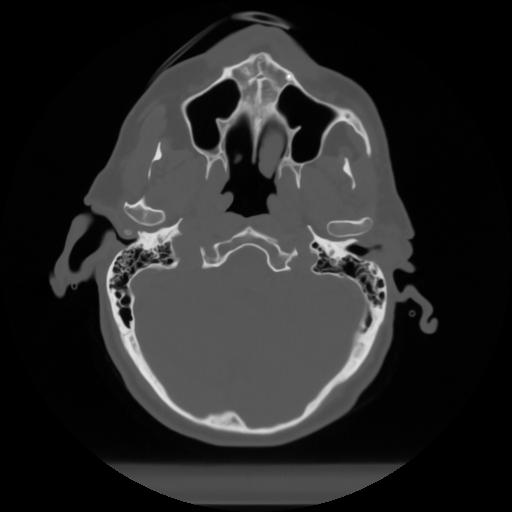

10 P.BLANDAS,,Axial,2.0,P.BLANDAS,,